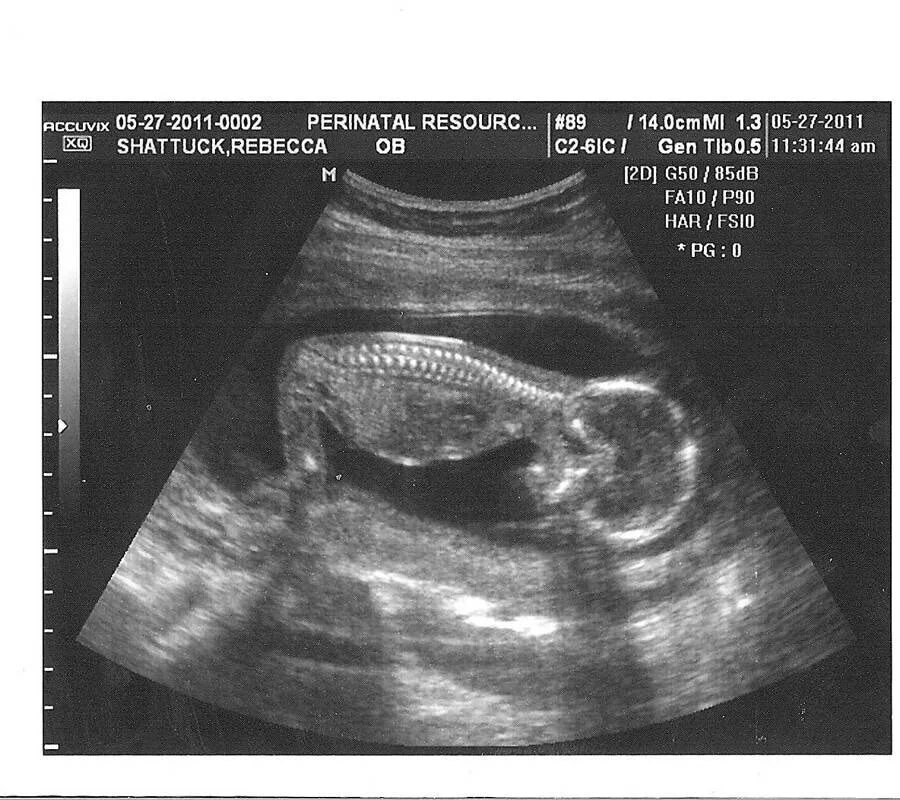

15 неделя беременности можно ли почувствовать шевеления